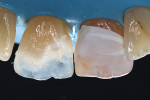

Several brands of composite resins that utilize nanotechnology are available, and each has its own unique mechanical and optical properties. Surprising differences can be seen when comparing the A3 body shades from various manufacturers. Shade guides exist to assist dental professionals in their selection; however, quite often, the material of the shade guide does not correlate to the restorative material that is being used. Blind application of these guides to determine shade can often result in a suboptimal esthetic integration. Creating custom shade guides from each system can be useful, but it is a time-consuming option. Therefore, before undertaking a procedure, it is recommended that clinicians perform a direct trial of several shades of the chosen material system on the teeth (Figure 1) and determine the correct choice from an assessment of clinical photographs. This also helps in the patient consent process as they can be directly involved in the choice of colors, reducing the risk of discontent after completion of the restoration.